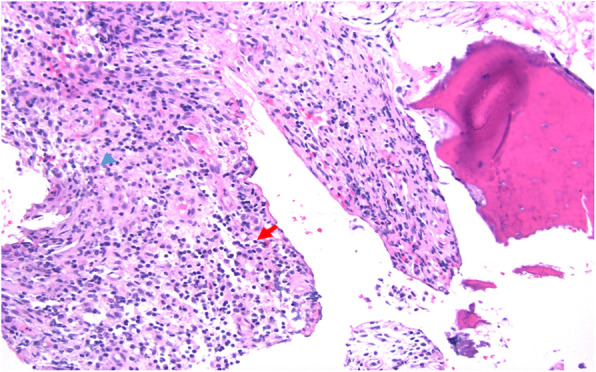

Fig. 5.

Acute and chronic osteomyelitis with areas of marrow fibrosis (red arrow) and dense lymphoplasmacytic inflammatory infiltrate (blue arrow)

Fig. 6.

Acute and chronic osteomyelitis with dense inflammatory infiltrate. Neutrophil (blue arrowhead) and lymphocyte (red arrow)